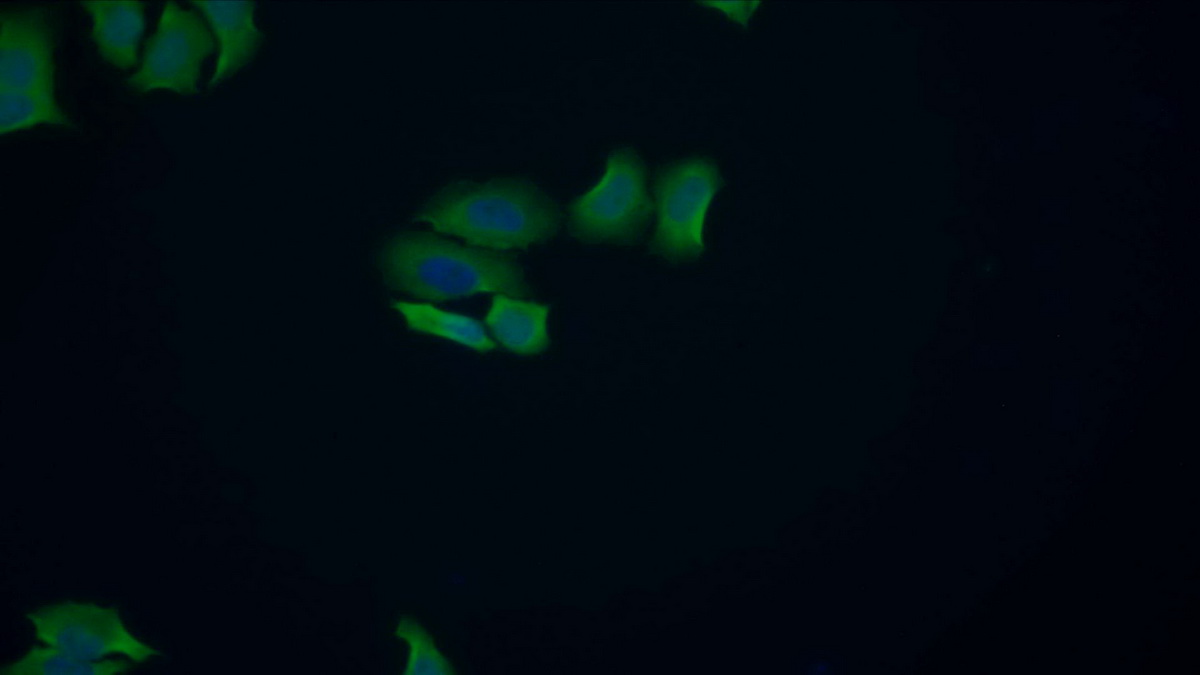

FITC staining on IF; Samples: Human MCF7 cell; Primary Ab: 20μg/ml Rabbit Anti-Human ACP1 Antibody Second Ab: 1.5μg/ml FITC-Linked Caprine Anti-Rabbit IgG Polyclonal Antibody (Catalog: SAA544Rb18)